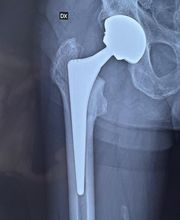

Il Dottor Pera Antonio esercita la professione medica presso il proprio studio ubicato a La Spezia, dove riceve su appuntamento. Pera dr. Antonio è medico chirurgo specializzato in Ortopedia e Traumatologia, anche infantile. Pera dr. Antonio è attualmente iscritto alla S.I.O.T.(Società Italiana di ortopedia e traumatologia); S.I.A.(Società italiana di artroscopia) di cui risulta essere socio onorario; A.L.A.(Associazione ligure di artroscopia); S.I.T.R.A.S.(Società italiana di traumatologia dello sport); S.P.L.L.O.T.(Società piemontese ligure e lombarda di ortopedia e traumatologia); Club di Chirurgia del ginocchio. Dal Gennaio 2012 Pera dr. Antonio svolge il ruolo di Delegato Regionale S.I.A.(Società Italiana di Artroscopia) per la Liguria. Riceve solo su appuntamento.